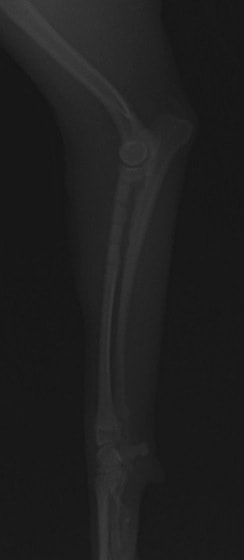

症例3:キルシュナーワイヤーのピンニングによる整復

ペルシャ猫 11ヶ月齢 雄

他院にて左大腿骨遠位の成長板骨折(salter-harrisⅠ型)が認められており、治療相談を目的として来院。当院にて、キルシュナーワイヤーを用いたピンニングにより骨折部位の整復を行いました。術後の経過は良好で、現在も経過観察中です。

術前レントゲン

術後レントゲン